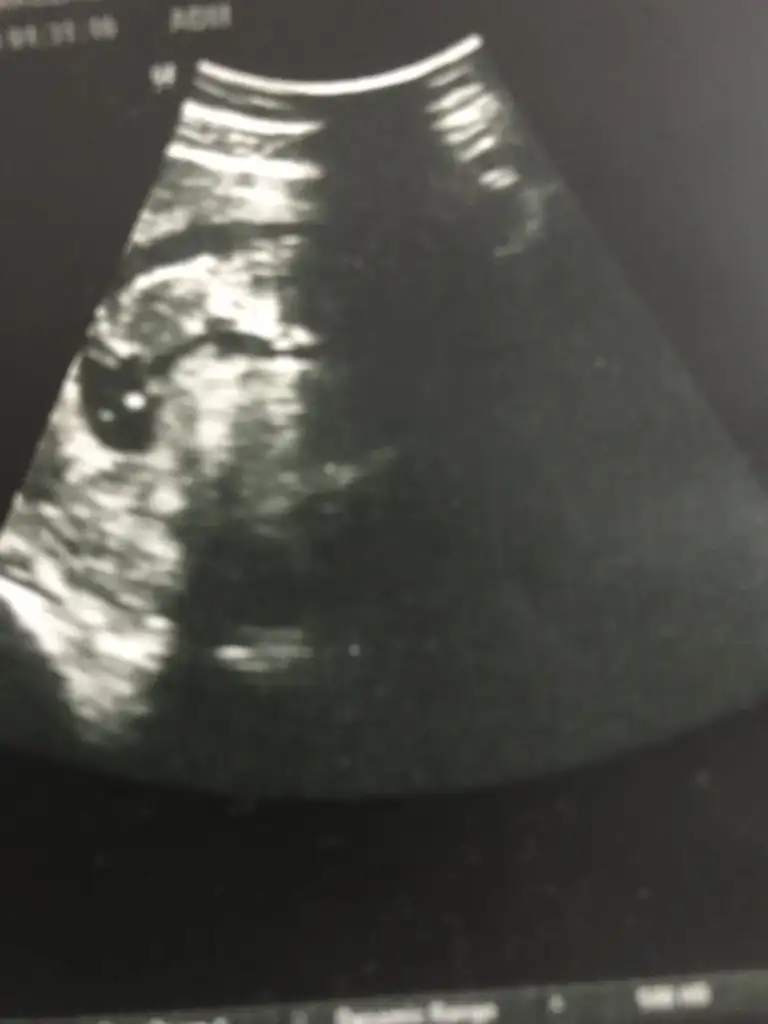

Bana da yorum yapar misiniz ?Tatlım kusura bakma, sık bakamıyorum şuan oturduğum yerden zor kalkıyorum

Bebeğin kız gibi![]()